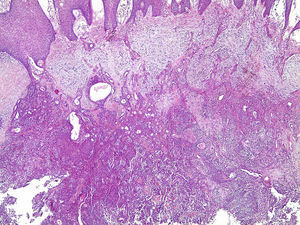

Os cortes histológicos, corados em hematoxilina e eosina, mostraram neoplasia de glândula salivar benigna, constituída por células epiteliais e mioepiteliais, parcialmente envolvida por fina cápsula de tecido conjuntivo fibroso (fig. 5). As células epiteliais encontravam‐se formando lençóis ou estruturas ductiformes, enquanto as células mioepiteliais formavam áreas mixoides, hialinas (fig. 6) ou exibiam aspecto plasmocitoide (fig. 7). O diagnóstico de adenoma pleomórfico foi confirmado. Paciente queixou‐se de desconforto no palato quando se alimentava, durante as 2 primeiras semanas após cirurgia. O paciente está sendo acompanhado clinicamente e, 2 anos após a cirurgia, não apresenta sinais de recidiva da lesão (fig. 8).

Os cortes histológicos mostraram neoplasia benigna de glândula salivar, envolvida por cápsula de tecido conjuntivo fibroso (fig. 14). O parênquima neoplásico é constituído por células epiteliais dispostas em lençóis e estruturas ductiformes, além de células mioepiteliais formando áreas mixoides e hialinas (fig. 15) ou apresentando‐se com morfologia plasmocitoide (fig. 16). O diagnóstico de adenoma pleomórfico foi confirmado. A paciente relatou ausência de dor no pós‐operatório e manteve utilização da placa de acrílico por 4 semanas. A paciente encontra‐se em acompanhamento e o exame clínico após 2 anos da remoção cirúrgica mostrou adequada cicatrização e ausência de sinais de recidiva da lesão (fig. 17).